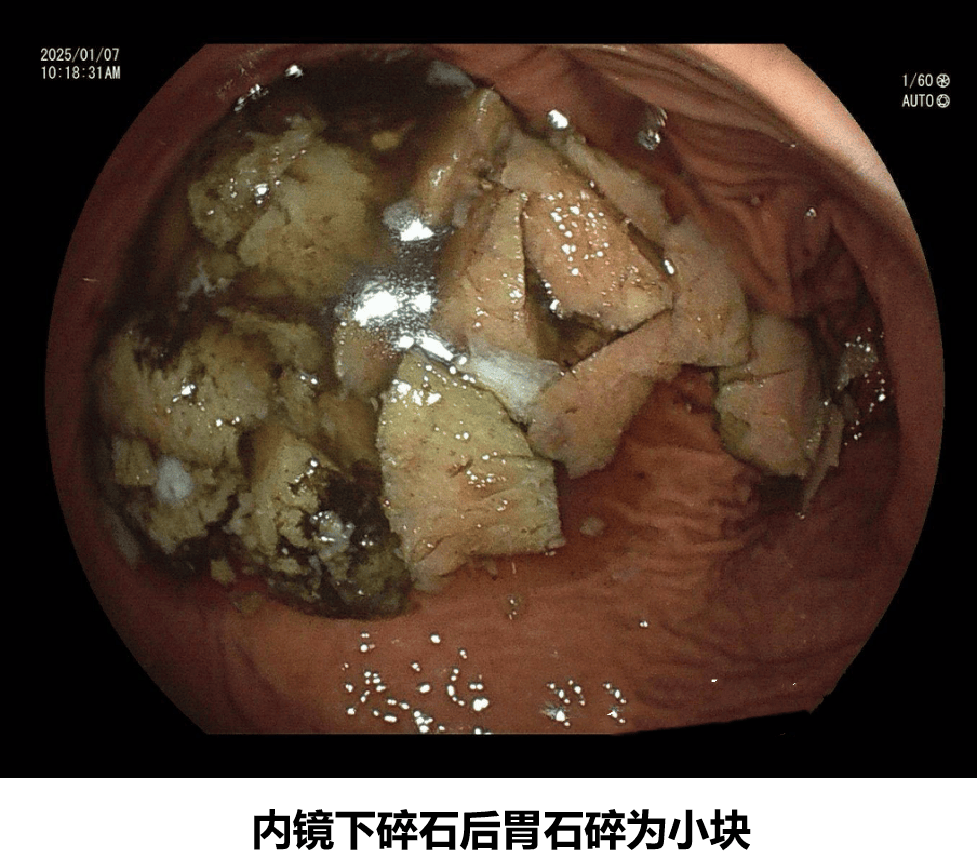

《中华消化杂志》曾报道一例患者连续三天每日食用3个以上火晶柿子后出现剧烈腹痛、恶心呕吐,经胃镜确诊为直径达4厘米的胃结石,最终需内镜下碎石治疗。因此,火晶柿子为何尽量少吃的核心原因之一就在于其潜在的鞣酸致石风险。